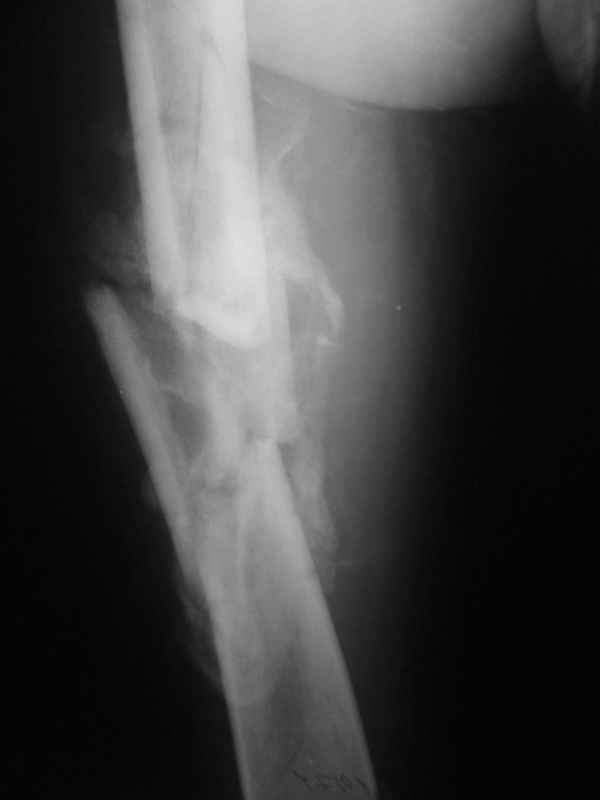

Re: Неправильно срастающийся оскольчатый перелом бедра

Конечно, снимки для планирования надо нормальные, не такой огрызок.

Можно закрыто мобилизовать отломки, наложить дистракционный аппарат, восстановить ось и длину, да и заштифтовать, на всякий случай с антибиотиковым цементным покрытием.

Спасибо за снимки. Предложения по тактике прежние.